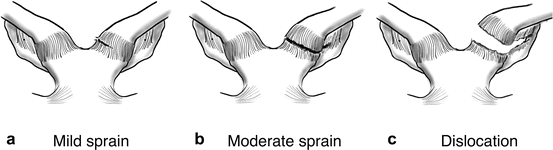

Diagnose this injury. Provide Moi, signs and symptomsand management

sternoclavicular joint sprain

moi - indirect/ direct impact

signs and symptoms: grade 1 - mild pain, point tenderness, no instability, grade 2 - moderate pain, swelling, point tenderness, joint sublaxation, inability to abduct/adduct through full rom , visable deformity, grade 3 - severe pain, swelling, complete disclocation , rupture of sternoclavicular ligament. posterio-retro sternal disclocation - medical emergecy (trachea and blood vessels

management - POLICE, immbolizatation in sling for 6 weeks